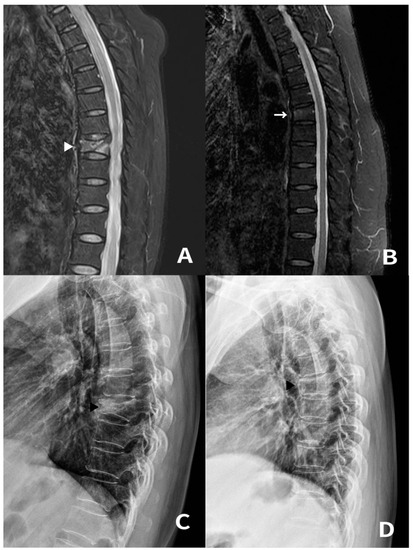

3.2. Case 3